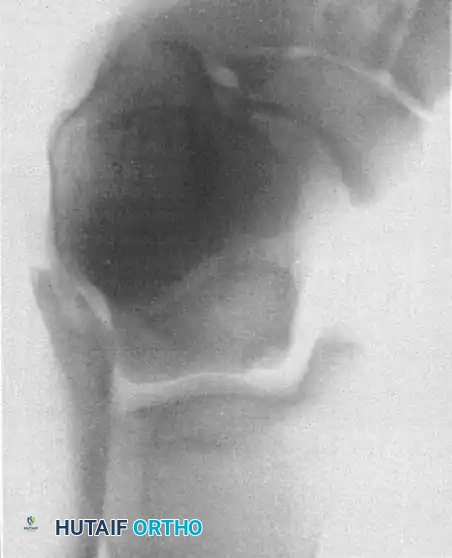

2. Osteochondral Autograft Transfer System (OATS)

Indicated for lesions > 1.5 cm², cystic lesions, or those that have failed primary microfracture.

* Technique: This procedure replaces the defect with hyaline cartilage (Type II collagen). Cylindrical osteochondral plugs are harvested from a non-weight-bearing portion of the ipsilateral knee (e.g., the lateral femoral condyle periphery) and press-fit into the prepared defect on the talus.

* Approach: Anterolateral lesions can often be accessed via a small arthrotomy. Posteromedial lesions frequently require a medial malleolar osteotomy for perpendicular access.

Fig. 16: Preparation for an OATS procedure. A medial malleolar osteotomy is performed to gain perpendicular access to a large posteromedial lesion.